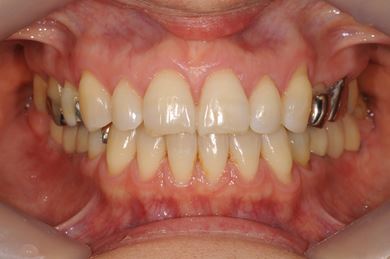

| 治療内容 | インプラント4本(抜歯即日スピードインプラント治療)、ハイブリッドセラミッククラウン6本 | ||||||||||||||||||||||||||||||||

| 総治療費 | 1,236,165円 | ||||||||||||||||||||||||||||||||

| 治療期間 | 1年5ヶ月 |